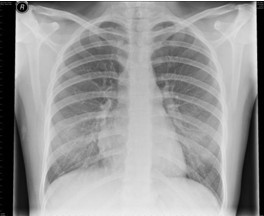

4.胸部X线检查 哮喘发作时两肺透亮度增加,呈过度充气征象:并发肺部感染、肺不张、气胸时出现相应X线征象。

【题】下列哪项描述符合哮喘发作时典型的X线表现

A.两肺透亮度增加,呈过度充气征象

答案:本题选A。